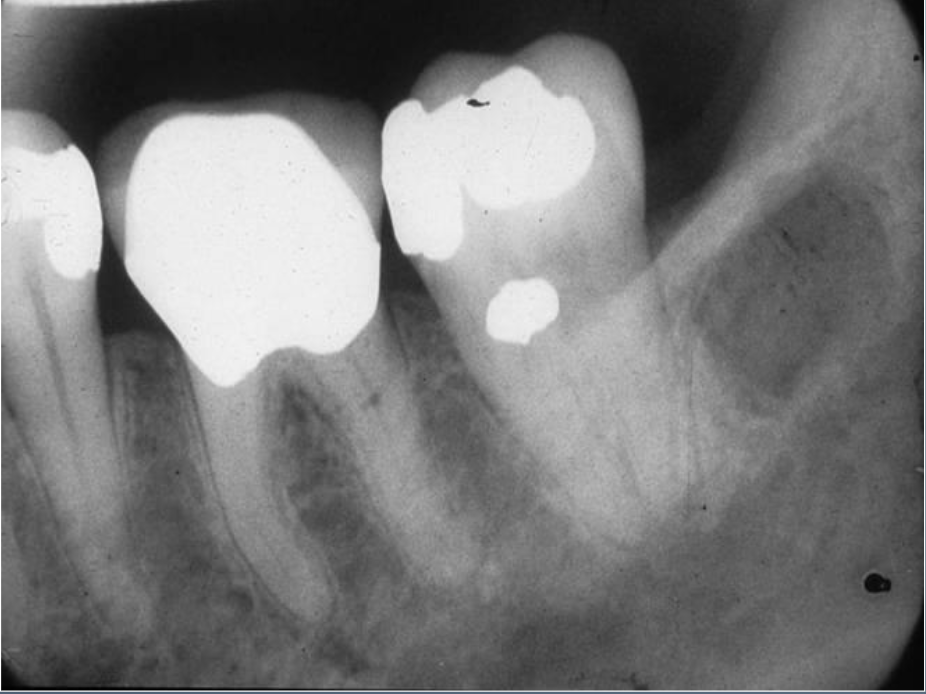

Q

What’s this?

IDIOPATHIC OSTEOSCLEROSIS